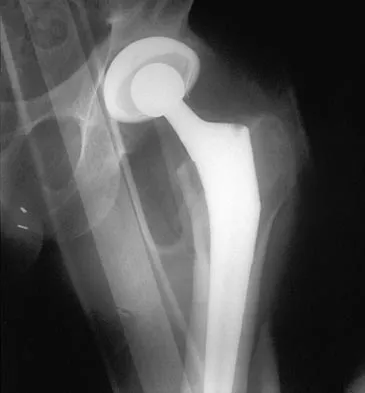

A 42-year-old man sustained the periprosthetic fracture shown in Figures 19a and 19b. The femoral component is well fixed. What is the next most appropriate step in management?

Explanation

The patient has a periprosthetic fracture below the femoral stem. The component is porous coated and well fixed. Open reduction and internal fixation, leaving the stem in place, can be performed when bone quality is good. Plating with or without allograft struts and supplemental cerclage fixation generally is acceptable. If the component is loose, revision to a longer device is recommended with appropriate stabilization of the fracture using the aforementioned methods. If bone loss has occurred, allograft supplementation or a tumor prosthesis may be indicated. Fractures located well below the stem tip can be treated without regard for the prosthesis. Closed reduction and bracing is not associated with good results for periprosthetic femoral fractures. Retrograde intramedullary nailing is not appropriate for this fracture. Duncan CP, Masri BA: Fractures of the femur after hip replacement. Instr Course Lect 1995;44:293-304.